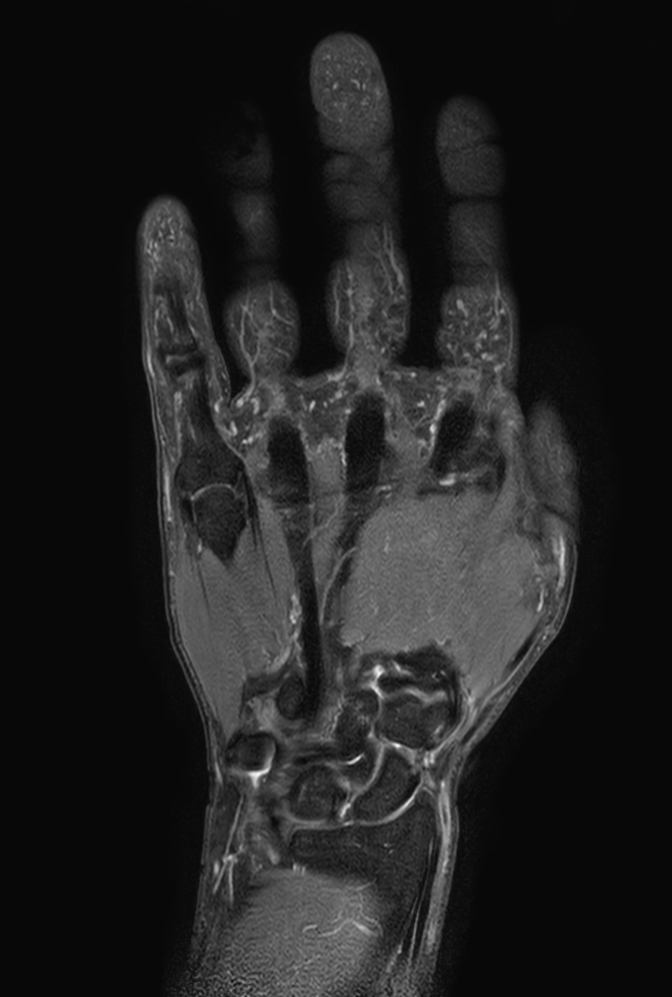

Coronal STIR TSE

-

Sagittal PDw TSE mDIXON XD (In Phase)